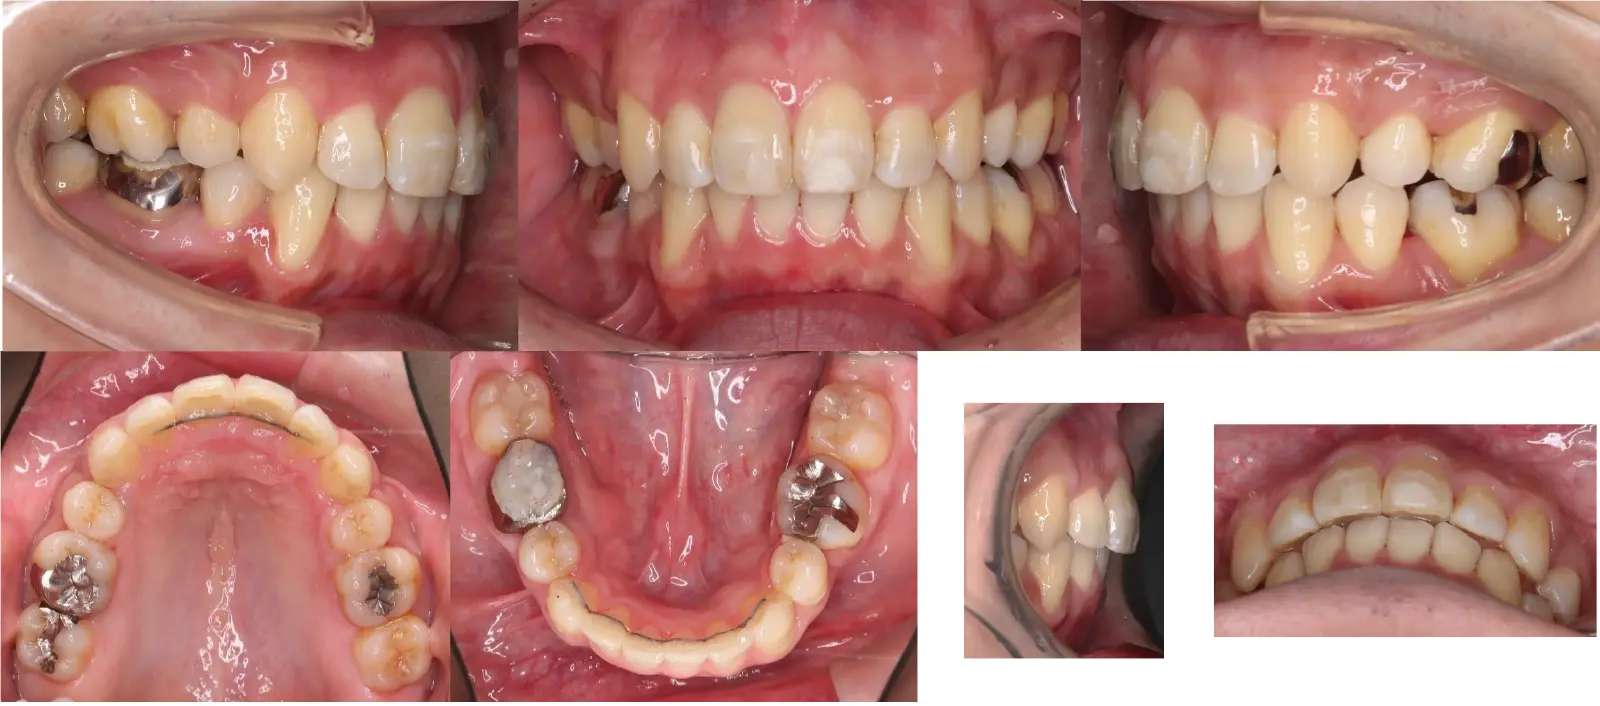

アングルⅡ級 叢生を伴う上顎前突症

- 主訴

前歯がかみ合わない、突出している

- 年齢

10代

- 治療期間

1年4ヶ月

- 治療回数

14回

- 治療に用いた主な装置

カスタムメイド型マルチブラケットタイプのデジタル矯正装置(インシグニア)

TAD(ミニスクリュー)を上顎臼歯部に植立

- 治療費

600,000円(税別)、調整料5,000円(税別)

※伊那分院にて治療

- 抜歯部位

上下顎第一小臼歯 計4本